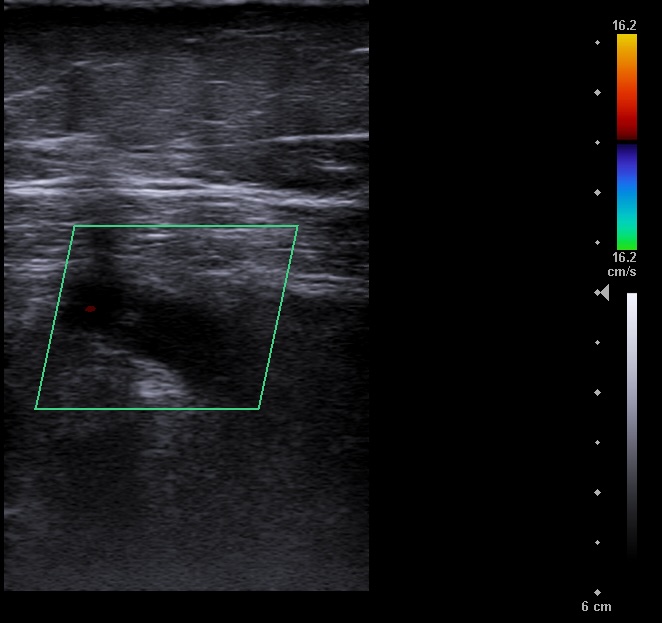

Vena poplitea no compresible, con material ecogénico en su interior y ausencia de flujo con Doppler color.